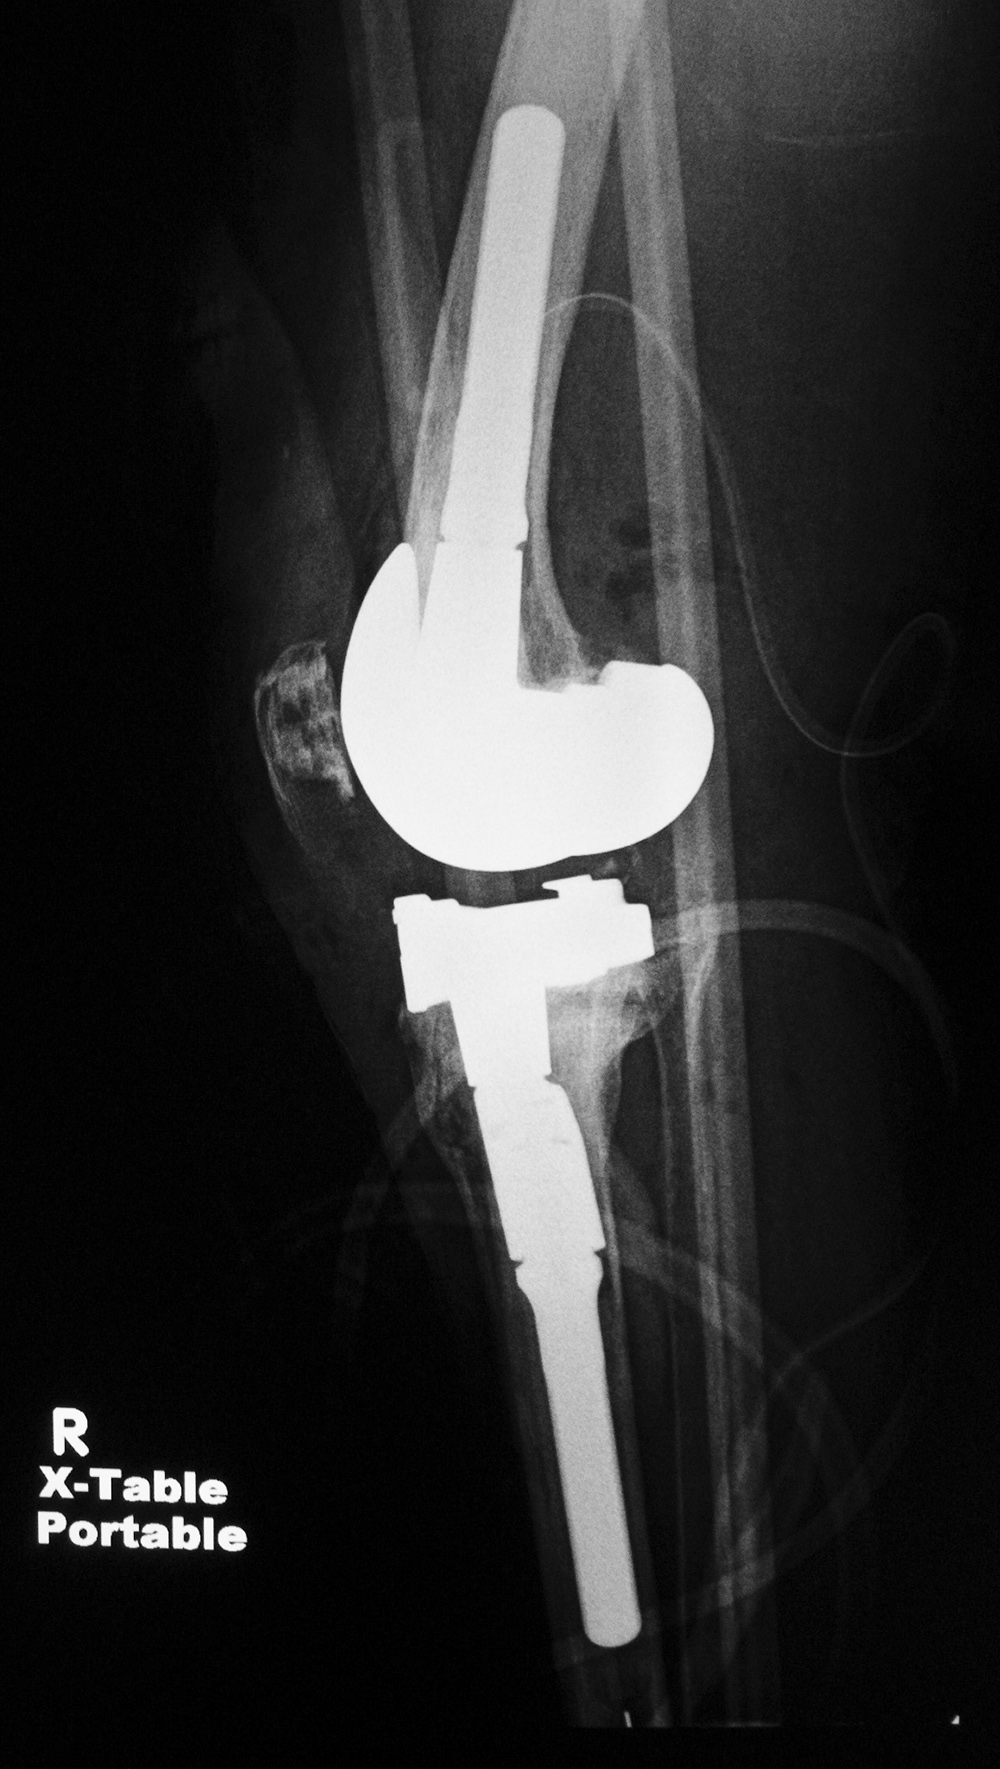

Biomet Vanguard 360 Revision Knee System |

This replaced a loose prior total knee arthroplasty. The patellar button was left in place. A surgical drain is in place, and there is subcutaneous gas from the recent surgery. |